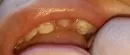

Ребенку 1 год 7 месяцев. Три месяца назад у ребенка прорезался жевательный верхний зуб с левой стороны. Две недели назад заметила затемненное пятнышко. Думала, что плохо прочистили зубки. Сейчас уже и на верхних передних зубах появились пятна, они рельефные, немного углубленные. На жевательном зубике тоже появилось углубление. Зубки нижние без пятен, беленькие, чистим силиконовым напальчником. Детского стоматолога в поселке нет, таких маленьких не принимают, единственный выход — ехать в город за 500 км от нас. Пока такой возможности нет.

По фотографии оценить деструкцию твёрдых тканей невозможно, но если она есть, то это свидетельствует о развитии генерализованного кариозного процесса.

В домашних условиях приостановить начавшийся кариозный процесс невозможно. Не следует затягивать, необходимо обратиться к детскому стоматологу-терапевту. Врач в случае развития кариеса проведет серебрение или озонотерапию для приостановки процесса.